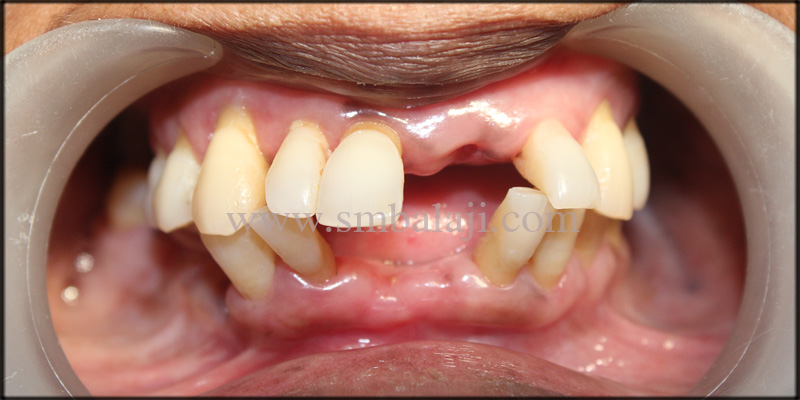

On intraoral examination, pus discharge from the lower anterior region was evident. The anterior teeth and the implant exhibited mobility. The surrounding gum tissues were red and swollen.

Full mouth X-ray (OPG) taken shows apicoectomy done to the root canal treated teeth in the lower anteriors. Infection around the implant and the teeth was evident.